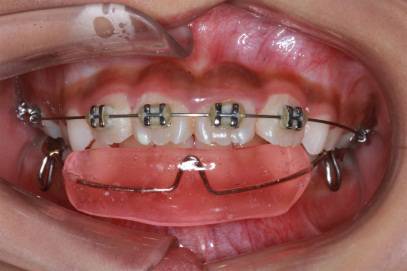

对于错牙合畸形的治疗,最常见的方式是正畸治疗。而对于一些严重的骨性畸形例如反牙合(地包天)、不对称牙颌面畸形等,则需进行正畸与正颌手术的联合治疗。

正 畸-正颌联合治疗矫治不对称牙颌面畸形